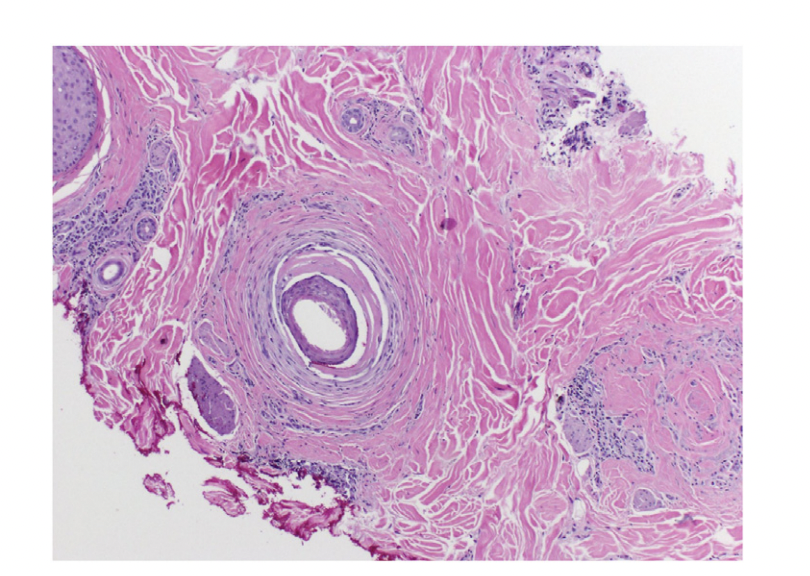

Histology from patient 3 showed premature desquamation of the root sheath, loss of sebaceous glands and follicular scarring and dropout. SOURCE: Lubov et al. Central centrifugal cicatricial alopecia in Black men: A case series highlighting key clinical features in this cohort. JAAD Case Reports 2023;38:27-31. Image used with creative commons license

Trichsocopy shows limited features sometimes although peripilar grey halos may be present. Histology does not always show loss of sebaceous glands in all CCCA but may in many. Eccentric thinning of the root sheath, premature desquamation of the inner root sheath, loss of sebaceous glands, perifollicular fibrosis and inflammation may be present.